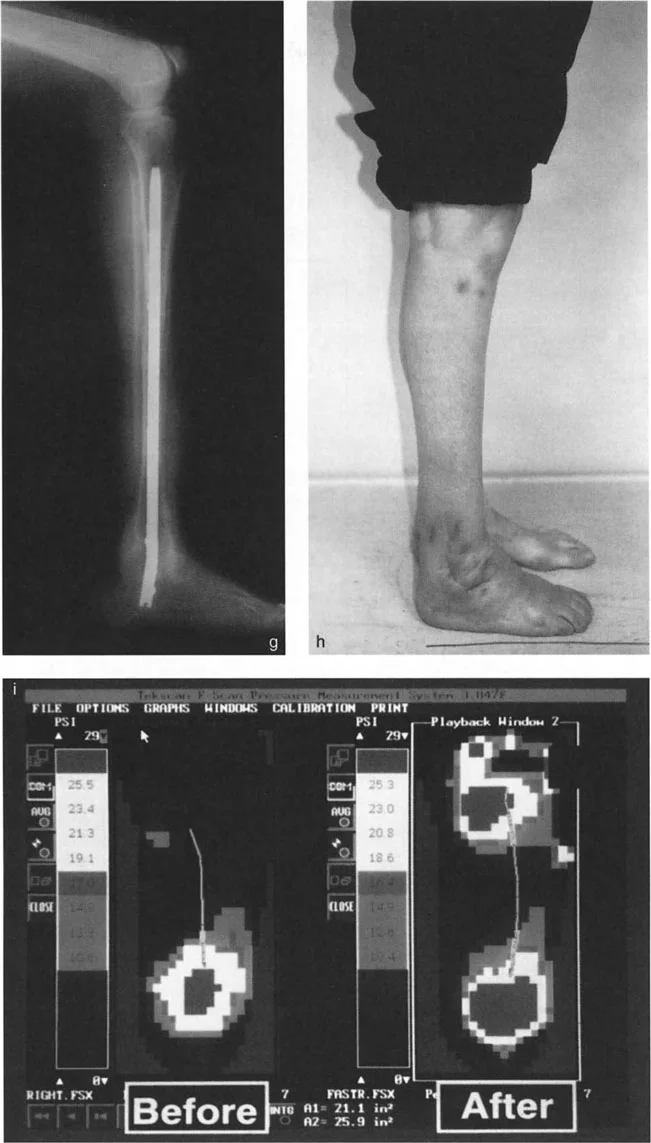

أنواع جراحات قطع العظم فوق الكاحل (Supramalleolar Osteotomy)

جراحة قطع العظم فوق الكاحل (SMO) هي الإجراء الأكثر شيوعًا لتصحيح تشوهات قصبة الساق البعيدة. تتضمن هذه الجراحة قطعًا دقيقًا في عظم الساق (القصبة) فوق مفصل الكاحل مباشرة، ثم إعادة محاذاة العظم وتثبيته في الوضع الصحيح. هناك عدة أنواع من هذه الجراحة:

• المميزات: يحافظ على طول الطرف، وهو مفيد إذا كان المريض يعاني أيضًا من اختلاف في طول الساقين.

• المميزات: يوفر استقرارًا عاليًا، ويسمح بالاتصال المباشر بين العظام، مما يسرع الالتئام ويسمح غالبًا بتحميل الوزن مبكرًا.

* فحص المشي (Gait Analysis): ملاحظة نمط مشي المريض لتحديد كيفية تأثير التشوه على حركته.

* منظر سولتزمان (Saltzman View): هذا المنظر الإشعاعي الخاص يتم الحصول عليه بزاوية 20 درجة لقياس محاذاة عظم العقب (Calcaneus) بالنسبة لقصبة الساق، وهو أمر بالغ الأهمية لتقييم تعويضات القدم الخلفية.